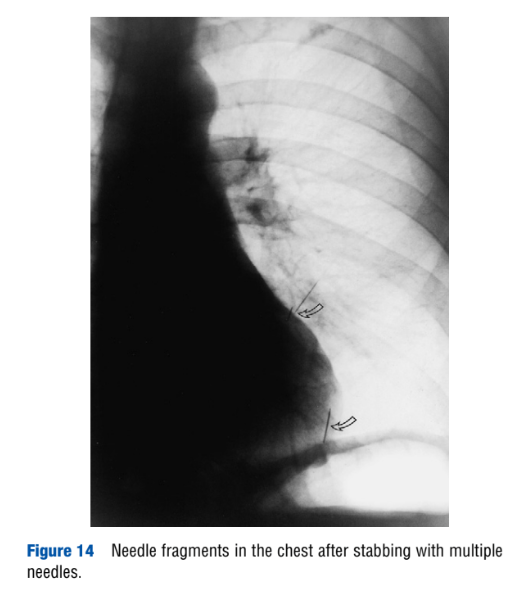

“Torture,” by H. Vogel. Encyclopedia of Forensic Sciences, second edition. 2013.